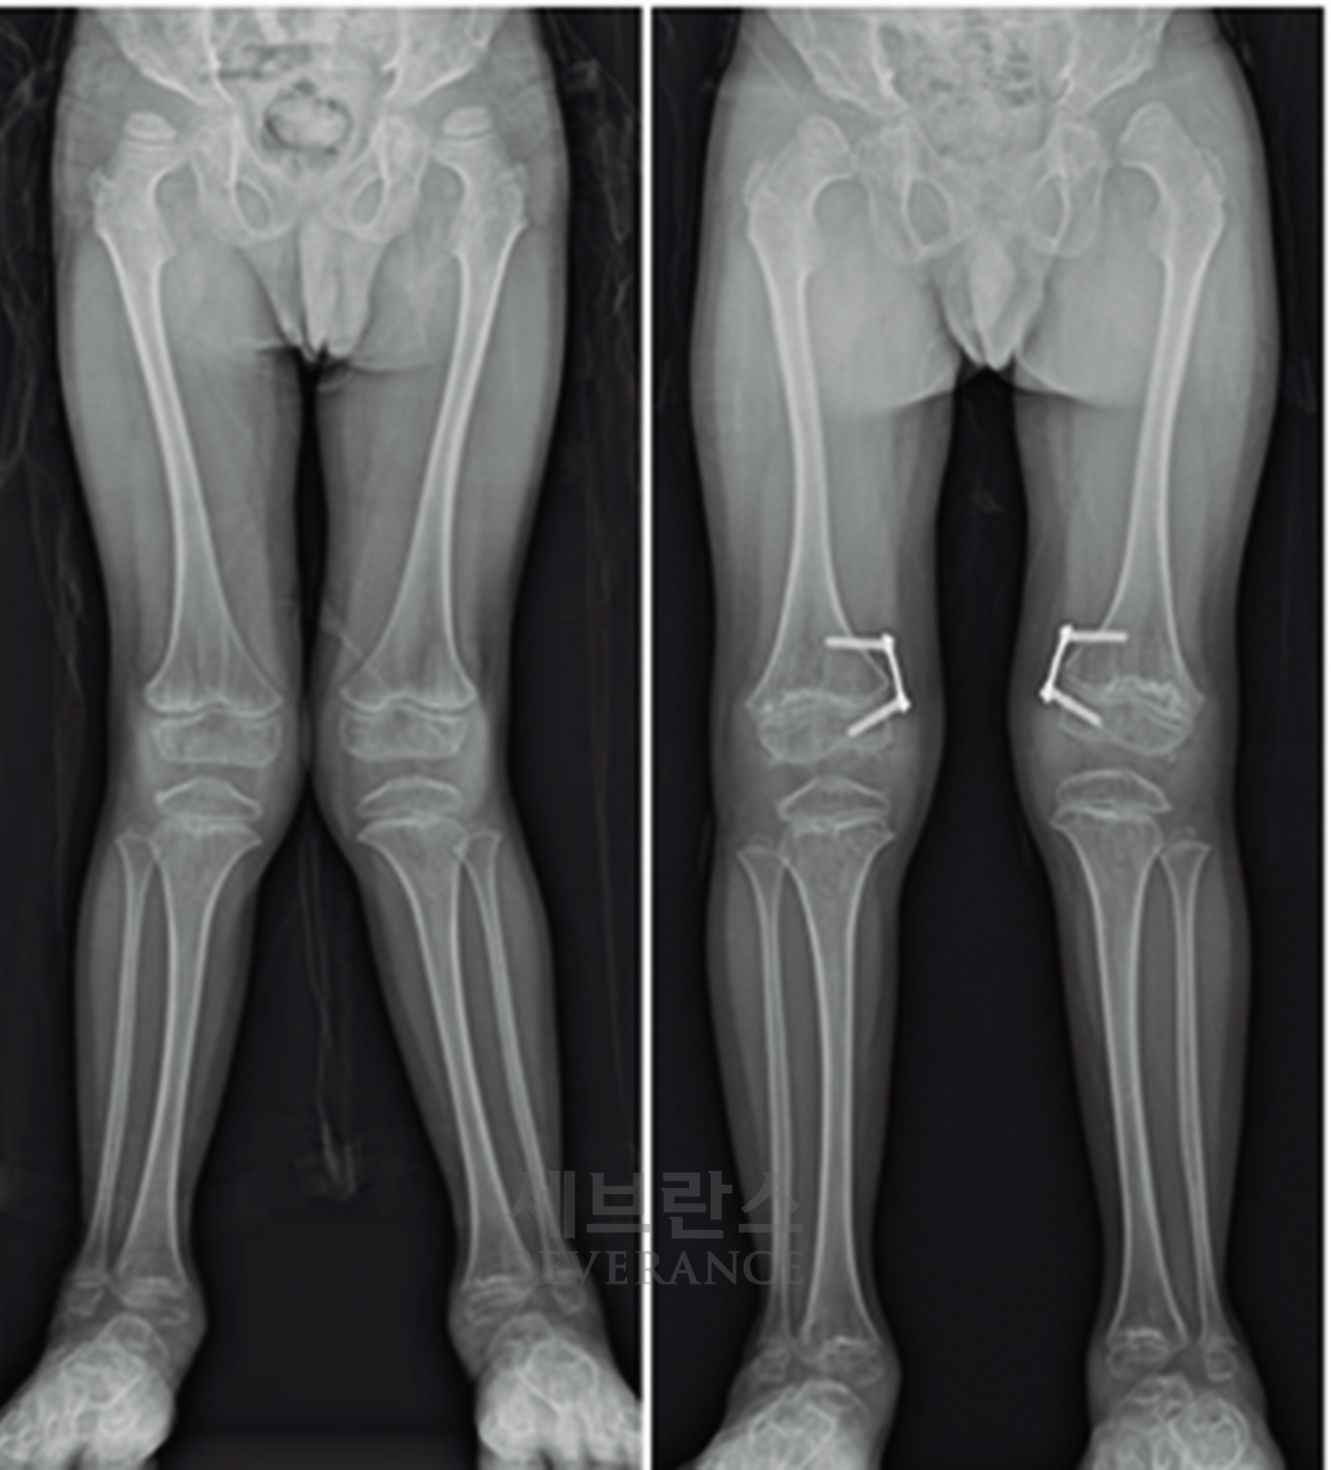

특발성 대사성 질환으로 인한 외반슬(X다리)에서 성장조절술을 시행한 환아성장판

성장판이 열려 있는 아이에게 많이 사용되는 성장조절술은 한쪽 성장판의 성장을 일시적으로 억제해 시간이 지나면서 다리 길이나 각도가 서서히 교정되도록 하는 방법입니다. 일반적으로 심하지 않은 O다리나 X다리, 경미한 다리 길이 차이에 적용합니다. 흉터가 작고 회복이 빠르지만, 효과가 나타나기까지 시간이 필요하고 성장이 끝난 아이에게는 사용할 수 없습니다. 또 교정이 완료된 후에도 성장 과정에서 일부 각도가 다시 돌아오는 ‘성장 반동’ 현상이 나타날 수 있습니다. 따라서 성장판이 완전히 닫힐 때까지 정기적으로 추적 관찰을 받아야 합니다.